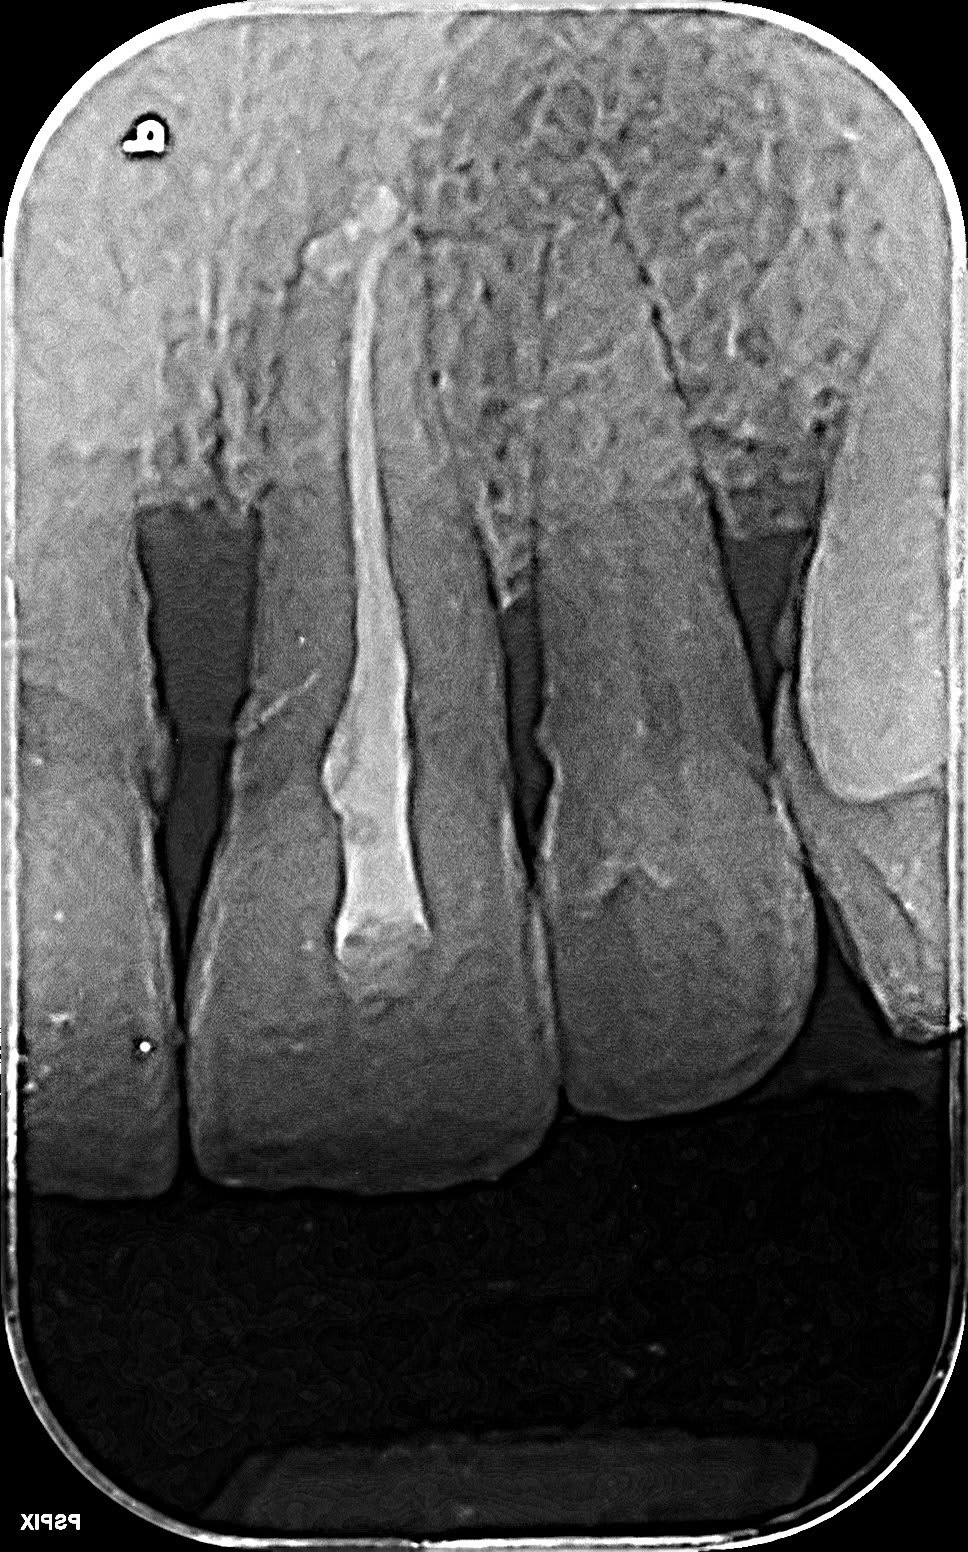

Par curiosité, vous en pensez quoi de la 36? La retro est mal cadrée, mais on voit ce qu'il y a à voir.

36 rpxsaf - Eugenol

On dirait un reliquat de tenon fibré dans la racine dl.

En mesial, région apicale il y a plein de différences de densités (?)

Derrière toute image, il y a une histoire.

La pré op, 5 ans plus tôt. Les lésions importantes laissent souvent une cicatrice.

(et pour savoir ce que j'ai laissé dans la mésiale, je ne m'en rappelle absolument pas; je parierai bien sur un mc spadden)

36 qdat1f - Eugenol